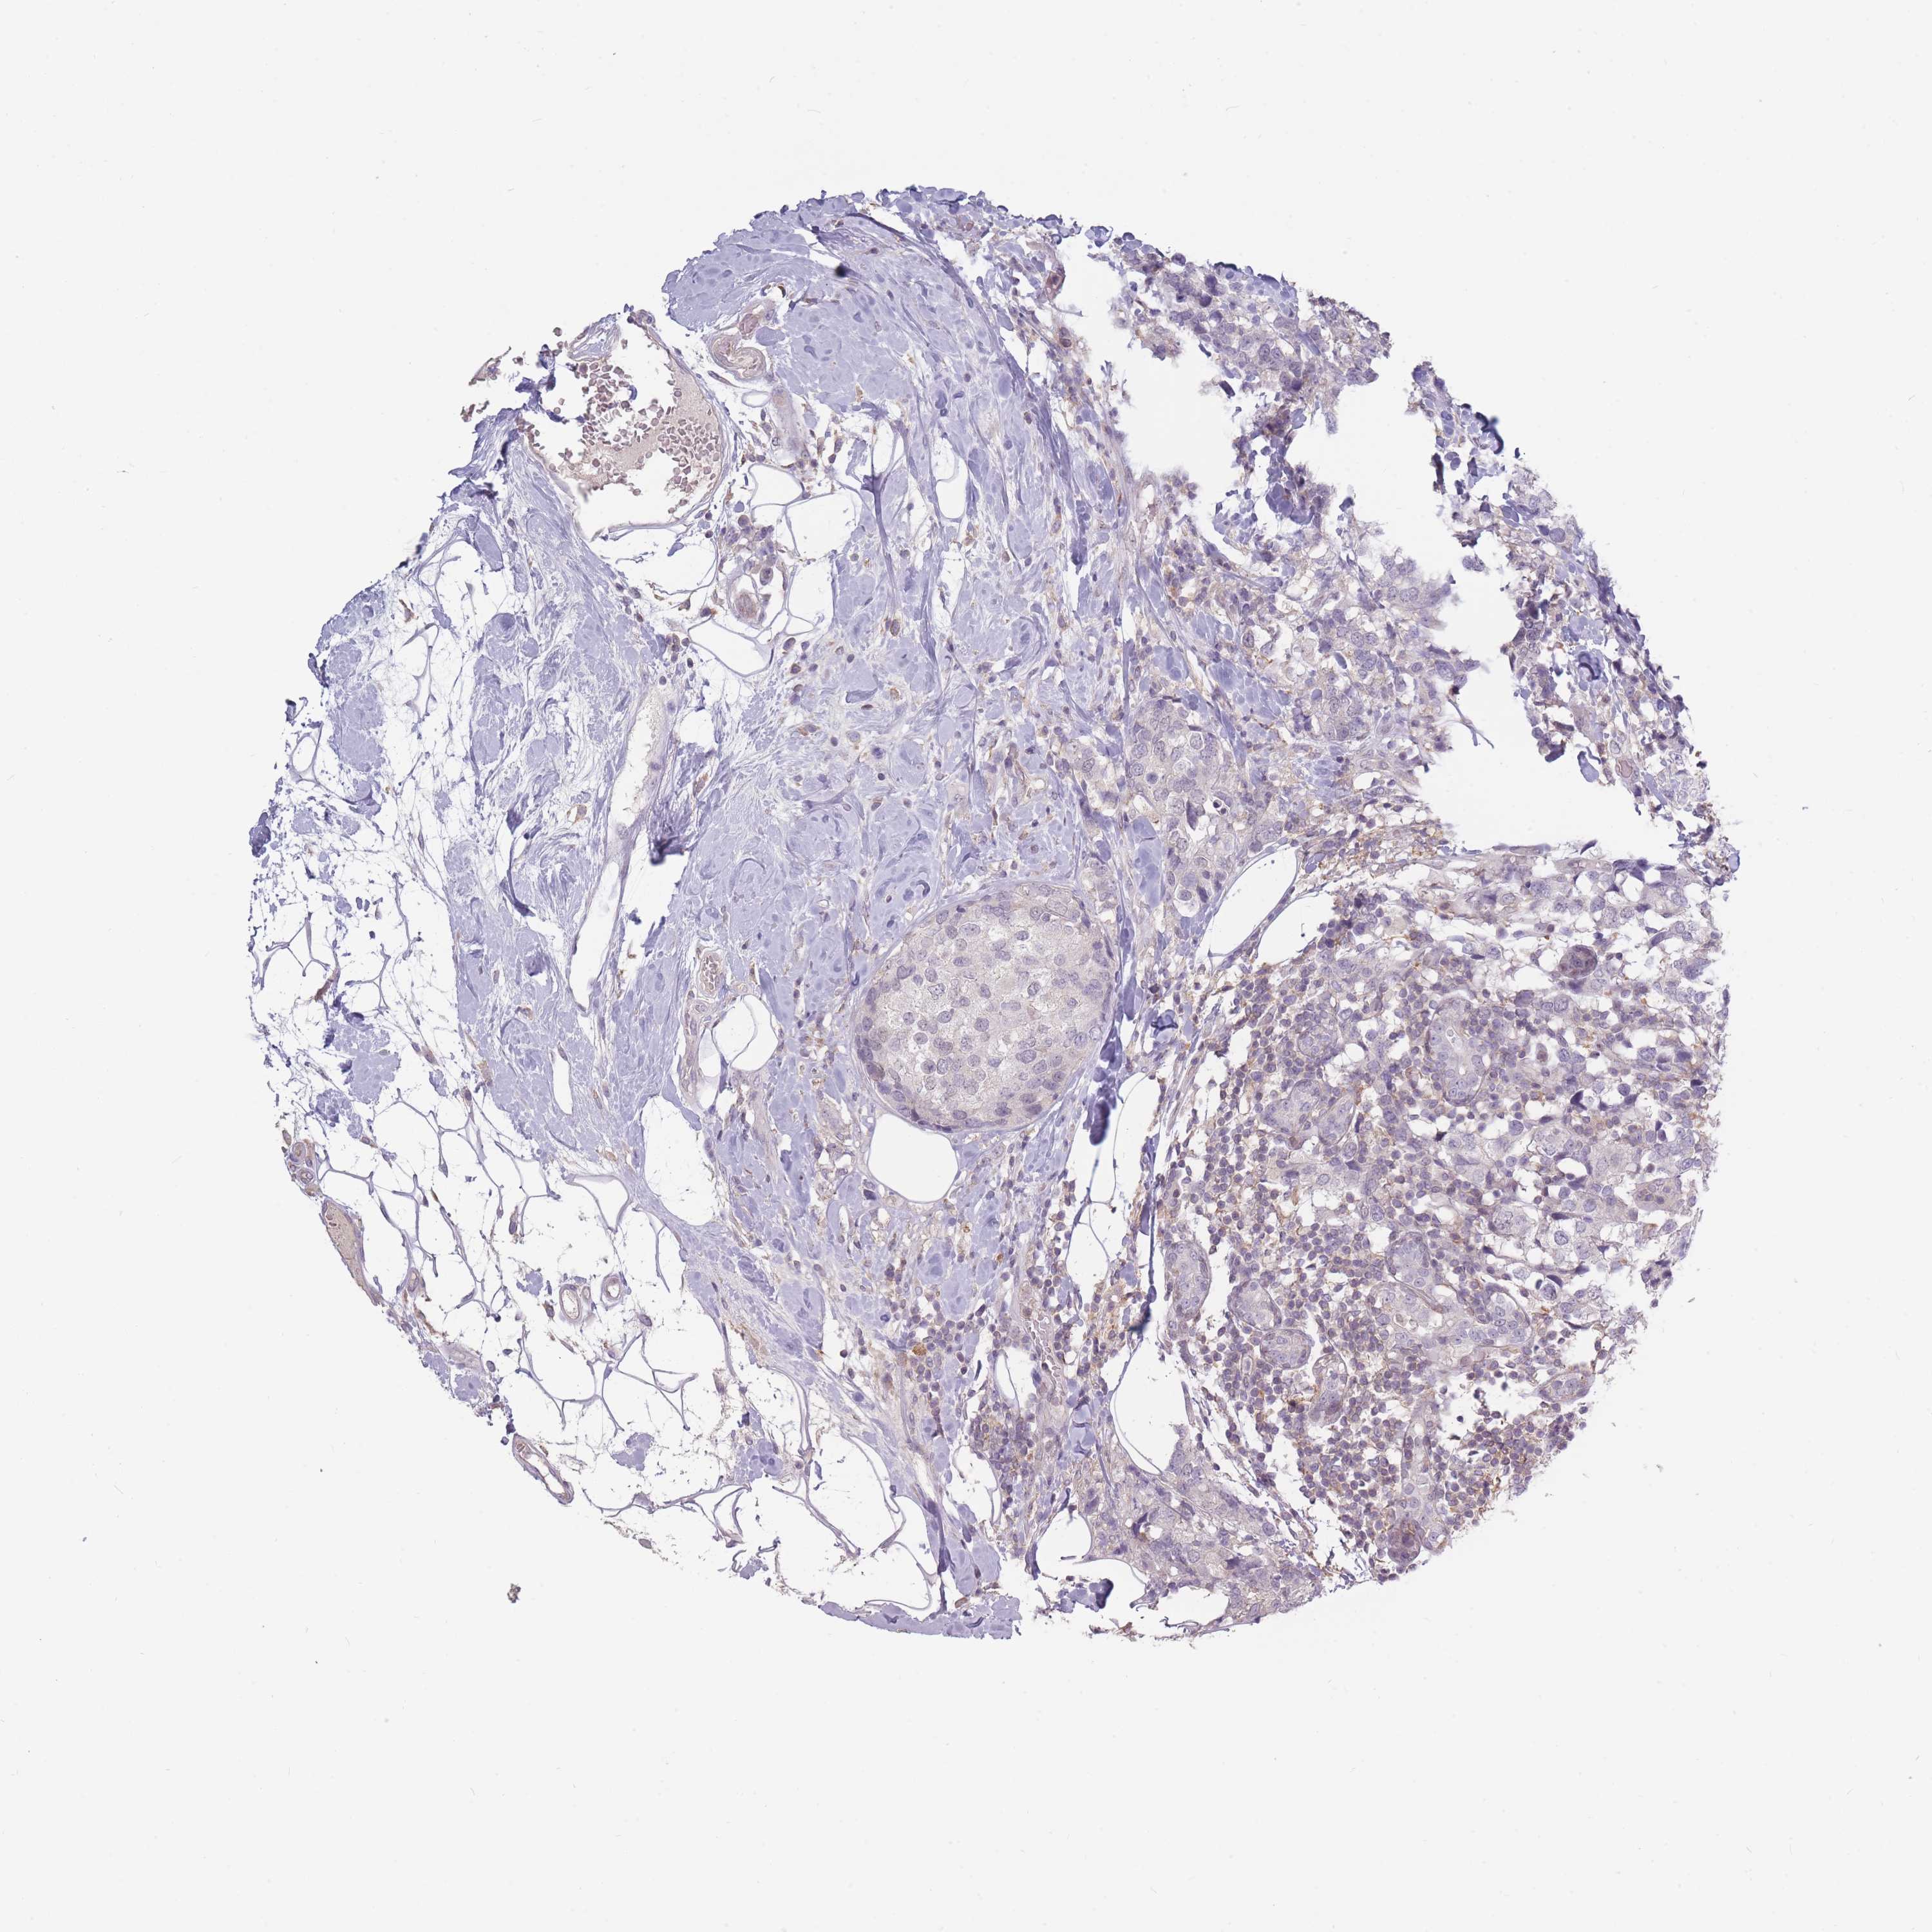

BRCA TCGA BRCA VALIDATION PROTEIN EXPRESSION

ANTIBODIES

AND

VALIDATION